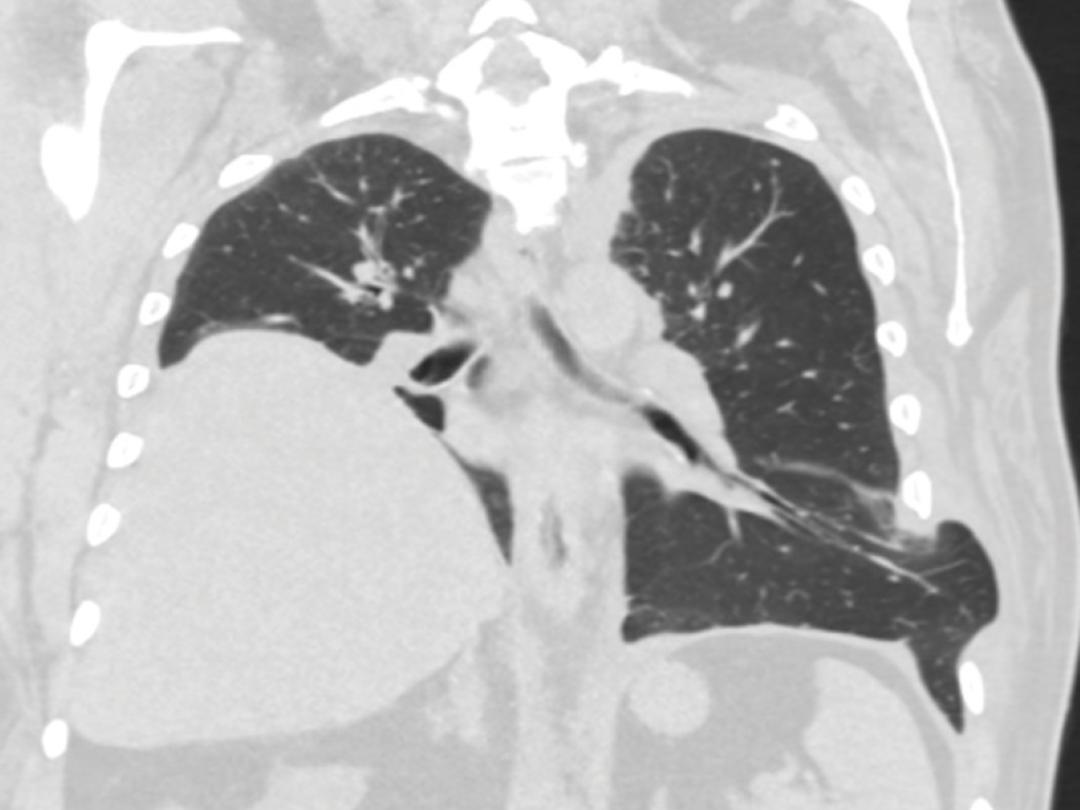

Een 66-jarige man kwam bij de huisarts met een sinds enkele dagen bestaande hoest. Hij was bekend met diabetes mellitus type 2, hypertensie en een bij toeval ontdekte hoogstand van de rechter diagfragmahelft met onbekende oorzaak. Omdat er op dat moment geen afwijkingen waren bij lichamelijk onderzoek, werd afgesproken om af te wachten.

Twee dagen later meldde de patiënt zich weer bij de huisarts. Na een stevige hoestbui was er pijn en een hematoom ontstaan in de linker flank (figuur a). Hij gebruikte geen antistolling. Het hematoom werd geduid als passend bij een gesprongen bloedvat. Gezien de klinisch stabiele…